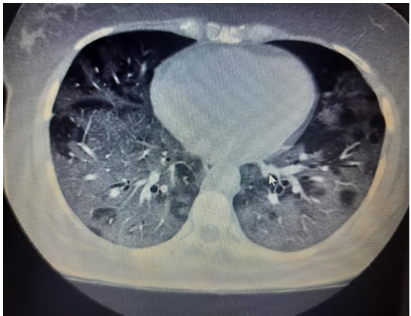

Fig. 3: Ground glass opacity (GGO) with septal thickening

Present study out of 107 cases 106 cases had abnormal HRCT findings out of which 99(92.5%) had bilateral abnormality and 7(6.5%) had unilateral abnormality and 7 had normal HRCT finding. Similar finding observed in [9] showed out of total of 175 chest CT scans were scored in this study. A total of 140 (80%) chest CT scans demonstrated bilateral infiltrates, and 31 (18%) chest CT scans showed unilateral infiltrates, whereas 4 (2%) chest CT scans had no abnormal findings. In our study, according to HRCT findings, GGO was seen in 70(65.4%) cases, consolidation in 34(31.8%), atelectatic band in 1(0.9%), crazy paving in 5(4.7%) cases, reticulation in 11(10.3%) cases, Peripheral hyperdensity in 9(8.4%), mediastinal LN and lymphadenopathy 2(1.9%) cases respectively, 1(0.9%) case with COPD, ground glass haziness, emphysematous changes, mild Fibrosis and septal thickening respectively. Similar findings observed in Sudhir Bhandari et al.119. (2020) showed that in an early phase of disease (10 d), among radiologically positive patients (8 out of 15) 12.50% patients had GGO, 75.00% patients had both GGO and consolidation, while remaining 12.50% patients had only consolidation in imaging of HRCT chest.